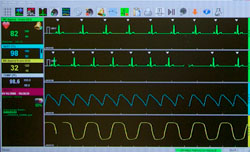

Telemetry

Telemetry

Telemetry allows us to continuously monitor multiple patients with an ECG when necessary. This allows us to diagnosis abnormal heart rhythms and closely monitor critical patients.

Monitoring

We have multiple machines to aid in the monitoring of our patients including: Pulse Oximeters, Blood Pressure Machines, ECG Monitors, Temperature Monitors, End Tital CO2 Monitors and Fluid Pumps.